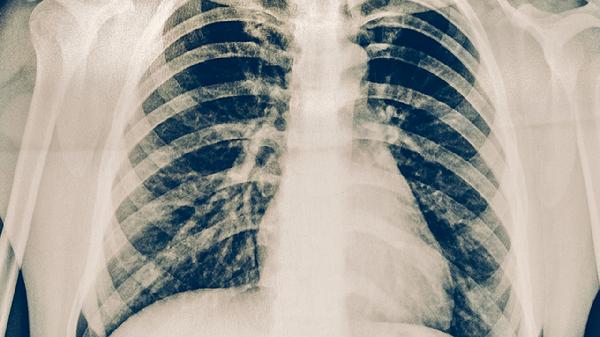

动物实验表明该药可加速结核结节纤维化,减少肺部空洞形成。在吡嗪酰胺片标准化疗基础上加用猫爪草胶囊,部分患者胸部影像学显示病灶吸收速度加快。

肺结核患者在使用猫爪草胶囊期间应保证优质蛋白摄入,每日进食鸡蛋、鱼肉等易消化高蛋白食物,适当补充维生素A、维生素D促进肺部修复。注意保持居室通风,避免剧烈运动导致咯血,治疗期间严格禁酒以减轻肝脏负担。需定期复查胸部CT和痰菌培养,全程规范用药才能达到理想治疗效果。